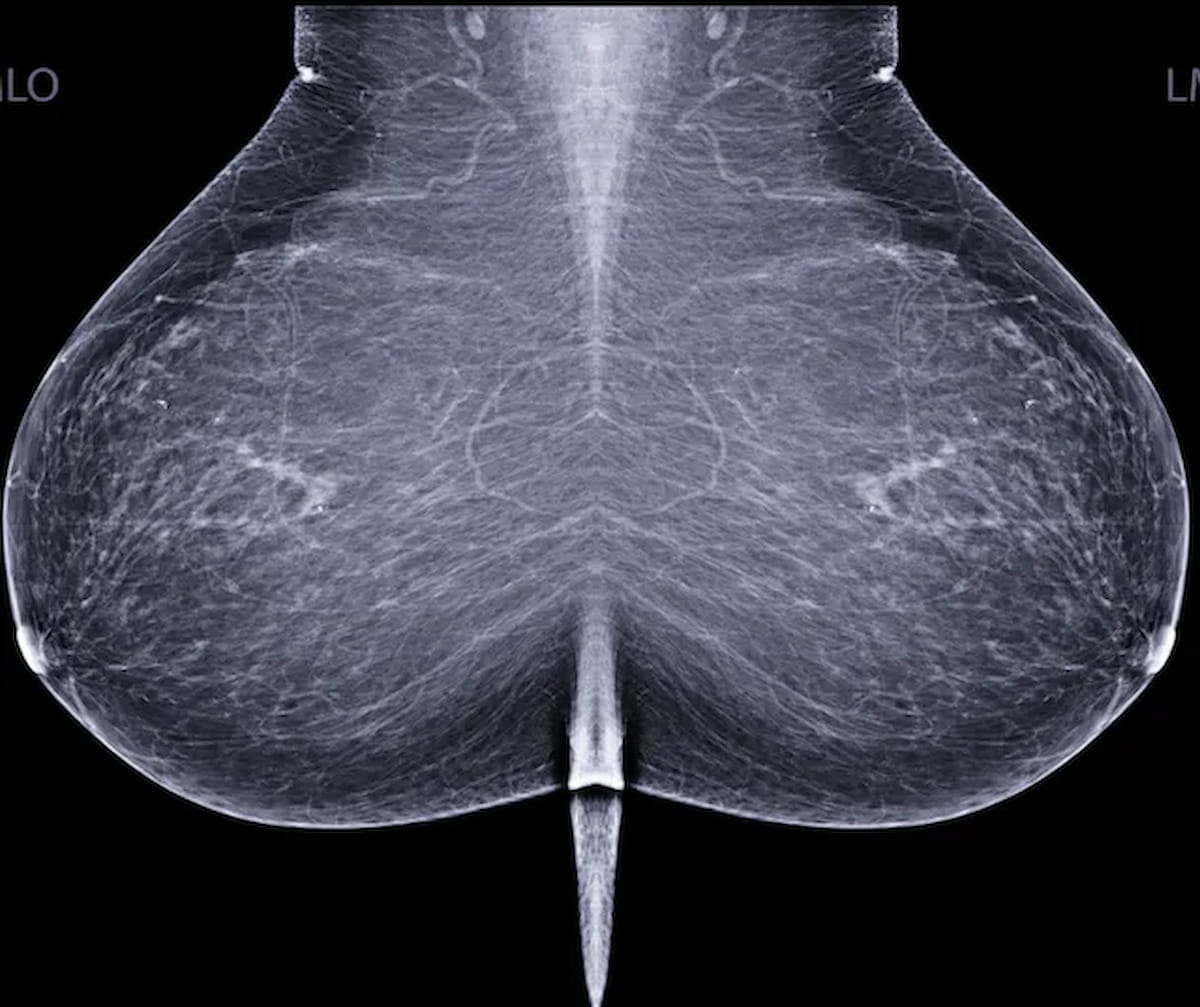

For women with dense breasts, abbreviated breast MRI and digital breast tomosynthesis (DBT) both offered greater than 98 percent sensitivity rates and greater than 94 percent negative predictive values (NPVs) for breast cancer detection, according to newly published research.